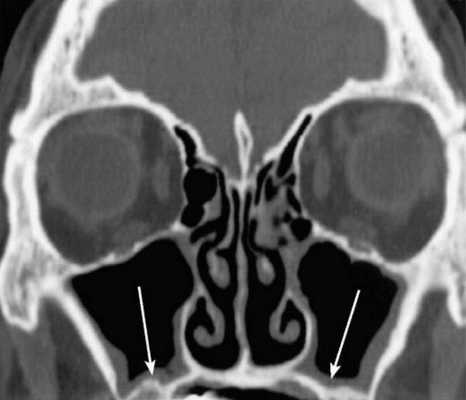

Концентрическая воспалительная гипертрофия ячеек решетчатой кости (указана стрелками)

- Сканирование (активный этап МРТ носовых пазух). Рентгенолог дает указание соблюдать неподвижность и включает томограф. Во время проведения процедуры лучше полностью расслабиться и успокоиться. Для профилактики искажения снимков нельзя двигаться, нежелательно открывать глаза. Сканирование длится 15 минут. При проведении МРТ с контрастным усилением процедуру прерывают для подачи усилителя. После внутривенной инъекции препарата работу томографа возобновляют. Применение контрастного вещества продлевает время исследования носовых пазух на 15 минут.